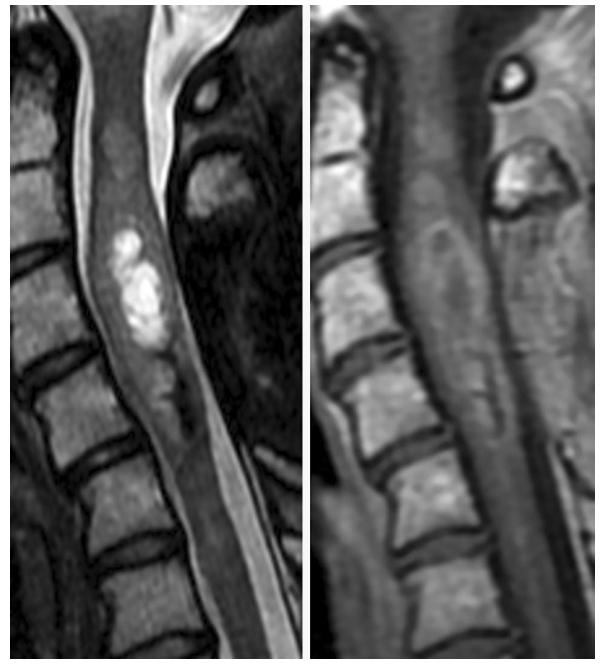

典型颈脊髓室管膜瘤的磁共振成像。多数病灶T2(左侧)高强度,边界清晰,局部脊髓扩张。T1造影剂(右侧)显示周围强化,低强化部分可能表现为囊变、坏死或出血

磁共振成像(MRI)是评估疑似脊髓肿瘤的较好方法,除非有禁忌症,否则可加或不加对比。灌注MRI和MR光谱学通常是没有用的,因为椎管的小直径和脊髓的运动与动脉血流。计算机断层扫描(CT)提供了很少的诊断效用,除了确定区域钙化,因此是一种替代,只有当MRI无法做到。在PET上,室管膜瘤细胞密度低,生长缓慢,典型的表现为代谢不足。脊髓扩张是鉴别髓内肿瘤的关键发现。室管膜瘤通常T1低,T2高,造影增强。通常包括囊变、出血、坏死和/或钙化区域,可产生异质信。大约60%的室管膜瘤伴有髓内囊肿,位于肿瘤的上端或尾部。粘液乳头状室管膜瘤常发生在脊髓圆锥区。影像学上特征性表现为异质性病变,细胞成分等强,黏蛋白产生或出血区域高强度(T1和T2)。这些轮廓清晰的肿瘤在造影剂作用下均匀增强。